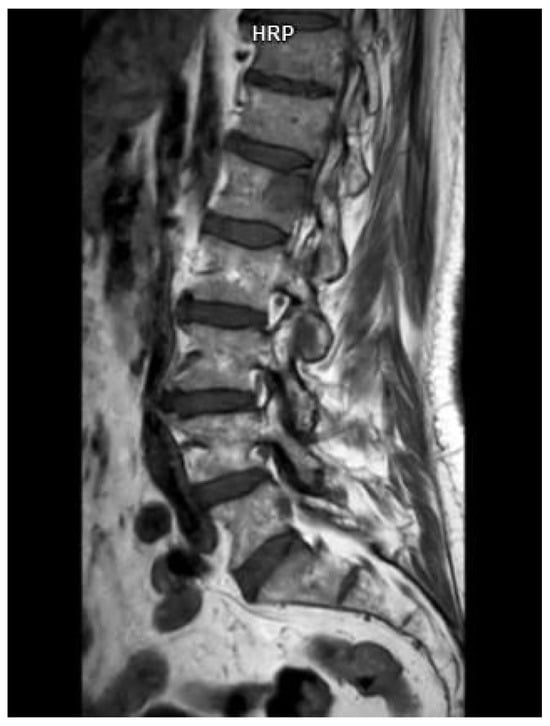

The presence of one or more sites of osteolytic bone destruction, at least 5 mm or greater in size, fulfills the criteria of bone disease in MM (CRAB), and therefore makes it necessary to initiate treatment (Figure 1, Figure 2 and Figure 3). In the case of smaller suspicious lesions seen in WBLDCT, they should be imaged within 3–6 months with CT or MRI to avoid overinterpretation [21,22].

Figure 1. A 77-year-old woman with a diagnosis of multiple myeloma. (A)—Whole-body low-dose computed tomography demonstrates lytic lesions in (A) vertebral bodies and (B) sacral bone and iliac crest. Source: Radiological Diagnostics Center, The National Institute of Medicine of the Ministry of Interior and Administration, Warsaw, Poland.